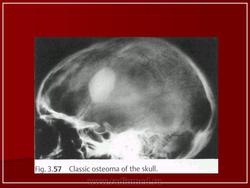

Остеома - первичная опухоль скелета, наиболее простая по гистологическому строению. Различают компактные, губчатые и смешанные остеомы.

Губчатые остеомы у детей встречаются крайне редко. Наиболее часто выявляются смешанные остеомы, локализующиеся в области ногтевой фаланги I пальца стопы и костях свода черепа.

Компактные остеомы обычно располагаются в костях лицевого скелета. Остеомы могут быть обнаружены в любом возрасте, однако время обращения к врачу не соответствует началу заболевания. Вследствие медленного роста и отсутствия клинических проявлений остеомы нередко диагностируют только у взрослых, которые помнят, что заболевание возникло у них еще в детстве.

Рентгенодиагностика остеом, как правило, не представляет трудностей. Рисунок опухоли является продолжением рисунка самой кости. Деструктивные изменения и нарушение коркового слоя всегда отсутствуют.

Остеома.